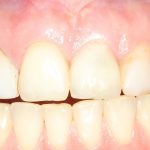

Рекомендации по установке имплантов. Для всех. Часть V.